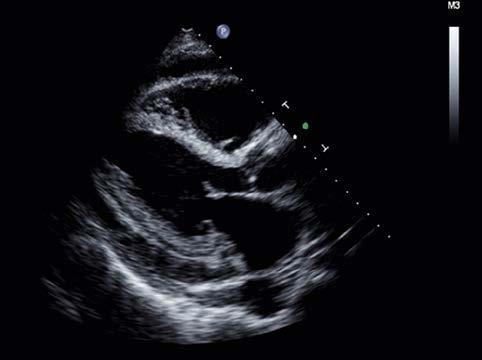

FIGURE 1-9 A, Ultrasound sent through a thin pie-slice–shaped volume of tissue produces an image commonly called a sector image or sector scan B, Sector scan of adult heart.